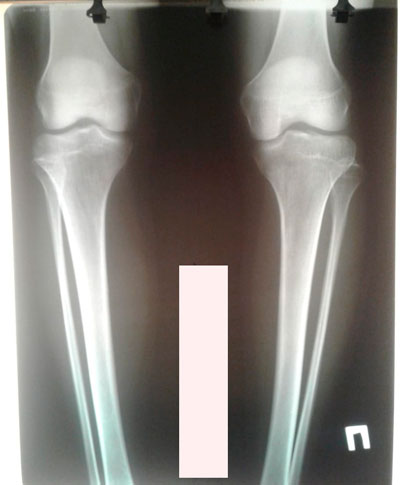

Дата операции - 20.06.2019г.

Исходник - 27 лет.

Ротация с обеих сторон.

Правая голень заметно тоньше, ратированее и деформированее.